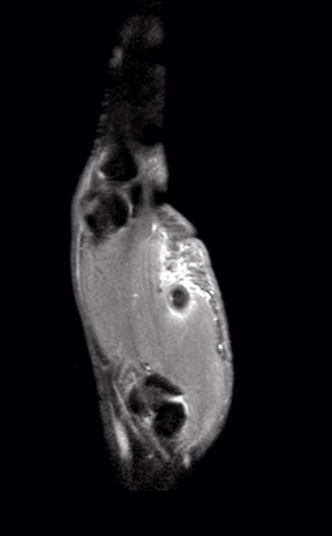

Motivo del estudio: Dolor a la flexión en el primer dedo con antecedente de lesión penetrante del mes de evolución que requirió sutura.

Técnica: Se realizó resonancia magnética de la mano izquierda en resonador de 1.5 teslas, con secuencias T1, T2, densidad protónica con y sin saturación de la grasa.

Es llamativo el aumento de la intensidad de señal del tejido celular subcutáneo en la región tenar de la mano y en el primer dedo.

El tendón flexor flexor largo del pulgar muestra pérdida de la continuidad en forma parcial a nivel de su trayecto sobre los metacarpianos, todo el tendón tiene aumento de la intensidad de señal en secuencias sensibles a líquido y se aprecia engrosado, el tendón se rodea por líquido.

Datos de rotura del tendón flexor largo del primer dedo (en zona flexora 3)

Edema de tejido celular subcutáneo.